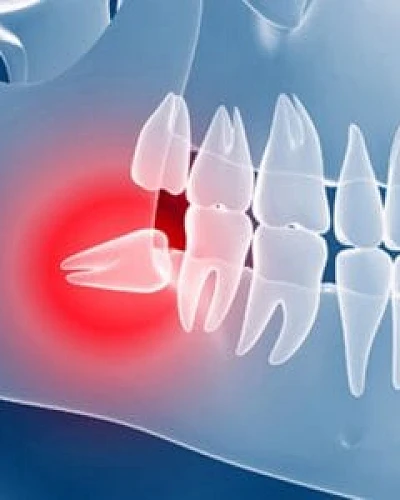

Dientes Retenidos

Resuelva las complicaciones de los dientes retenidos con nuestros protocolos quirúrgicos avanzados. Cuando un diente no erupciona correctamente, puede causar dolor, infección o daños en las raíces adyacentes. Nos especializamos en la extracción precisa de muelas del juicio impactadas o en la fenestración de caninos para su alineación ortodóncica. Mediante técnicas mínimamente invasivas, garantizamos la preservación del hueso y una recuperación cómoda.